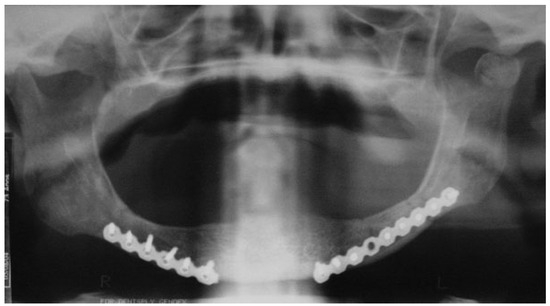

A 72-year-old man was referred to the University Hospital in June 2004 as a fall victim. After extraoral exam, mandibular X-rays showed two fractures at the left mandibular body, one in the left subcondylar region with minimal displacement and one at the right mandibular body (Figure 1 and Figure 2). The patient presented mouthopening limitation, and besides the painful symptomatology during palpation, the patient reported dysphagia and paresthesia of the mental nerve bilaterally and stated that he did not wear dental prosthesis.

Figure 1. Preoperative posteroanterior mandibular radiograph.